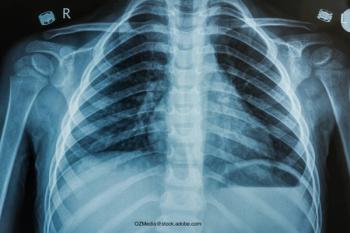

In cases of poorly controlled disease, even with good medication adherence, it might make sense to turn to biologics. A presentation at the virtual 2021 American Academy of Pediatrics National Conference & Exhibition covered biologics available for treating asthma and allergic skin disease.